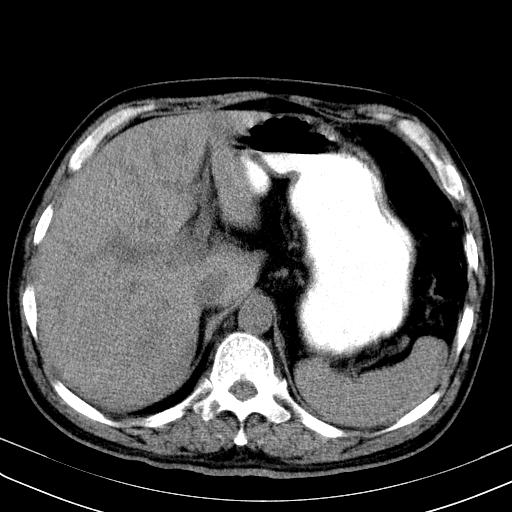

先行ct平扫,纵膈内多发软组织影,ct值约为36hu,以下为增强扫描和腹部平扫。

经典?纵膈多发肿大淋巴结。腹膜后未见异常。

1)考虑淋巴瘤。2)双侧少量胸腔积液。

大家看看肝脏右叶片状低密度影是什么改变啊?

淋巴瘤?肝脏请增强后说啊

多发肿大淋巴结影,肝内改变需结合强化观察

多发肿大淋巴结影,肝内改变需结合强化观察。